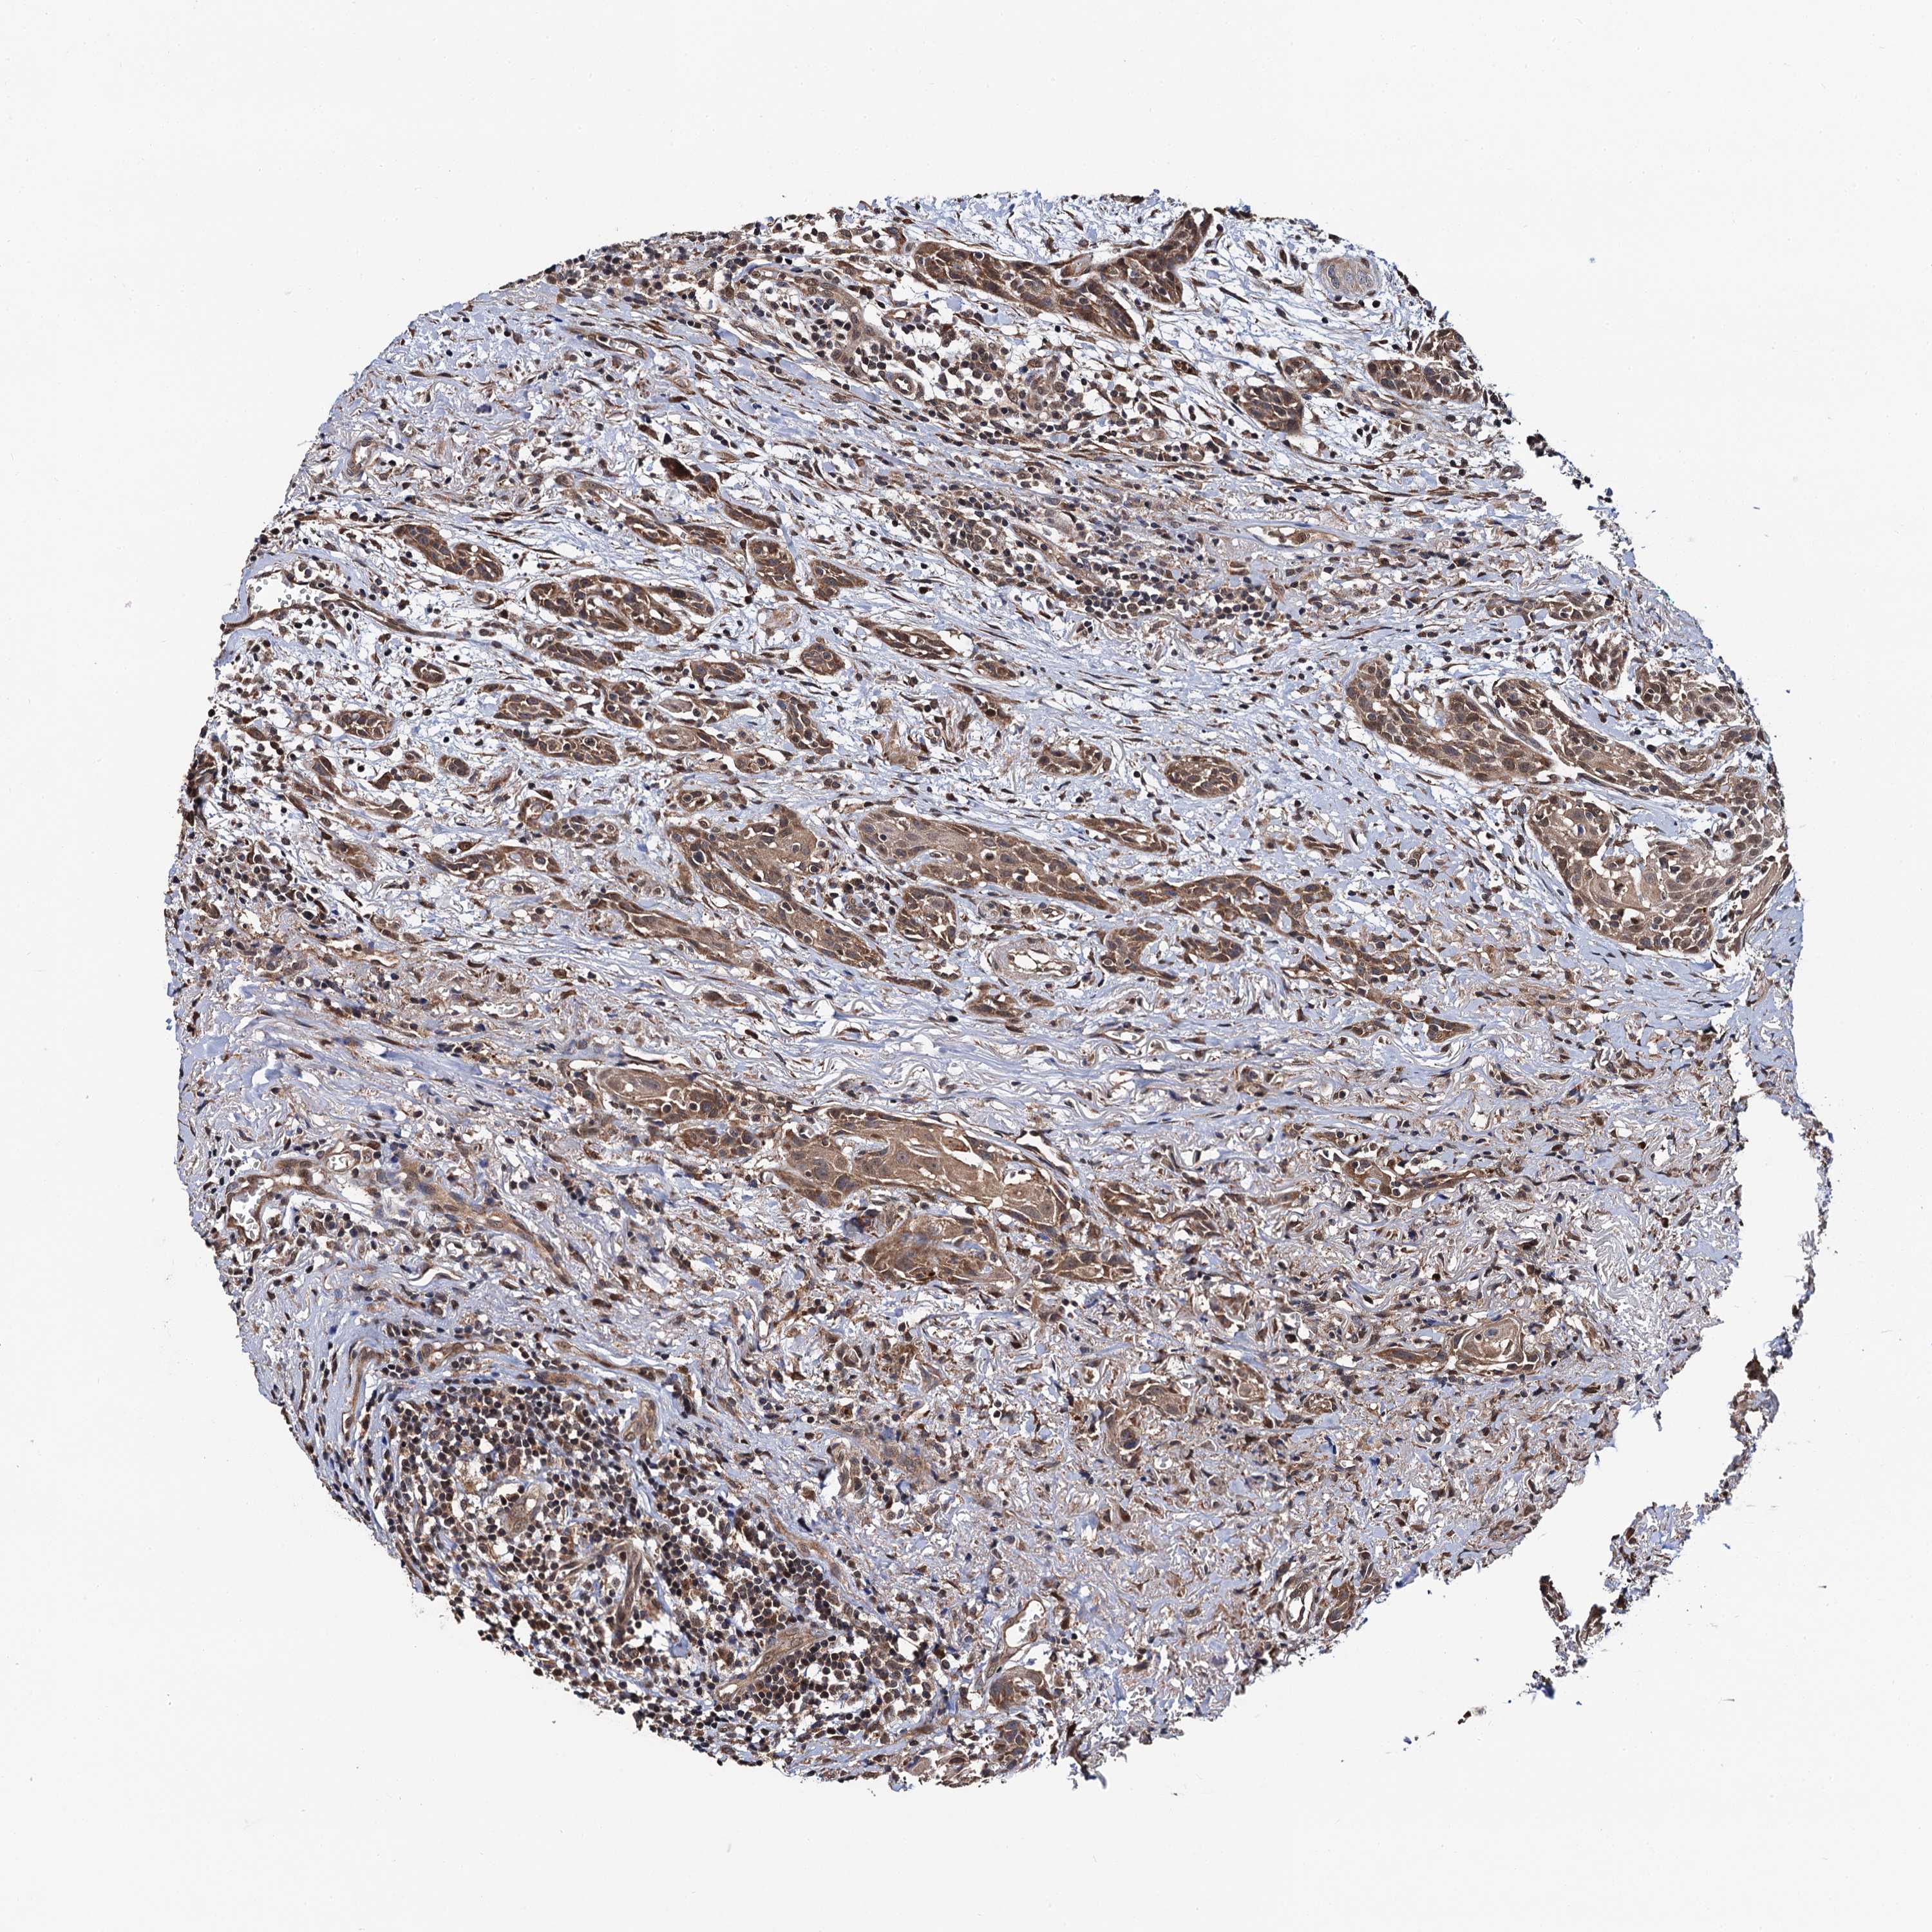

HEAD AND NECK CANCER - Protein expressioni

A mouse-over function shows sample information and annotation data. Click on an image to view it in a full screen mode. Samples can be filtered based on level of antibody staining by selecting one or several of the following categories: high, medium, low and not detected. The assay and annotation is described here.

Antibody stainingi

Antibody staining in the annotated cell types in the current human tissue is reported as not detected, low, medium, or high, based on conventional immunohistochemistry profiling in selected tissues. This score is based on the combination of the staining intensity and fraction of stained cells.

Each image is clickable and will lead to virtual microscopy that enables deeper exploration of all samples and also displays staining intensity scores, fraction scores and subcellular localization as well as patient and tissue information for each sample.

Antibody HPA041439

Staining

High

Medium

Low

Not detected

Intensity

Strong

Moderate

Weak

Negative

Quantity

>75%

75%-25%

<25%

None

Location

Nuclear

Cytoplasmic/membranous

Cytoplasmic/membranous,nuclear

Squamous cell carcinoma, NOS